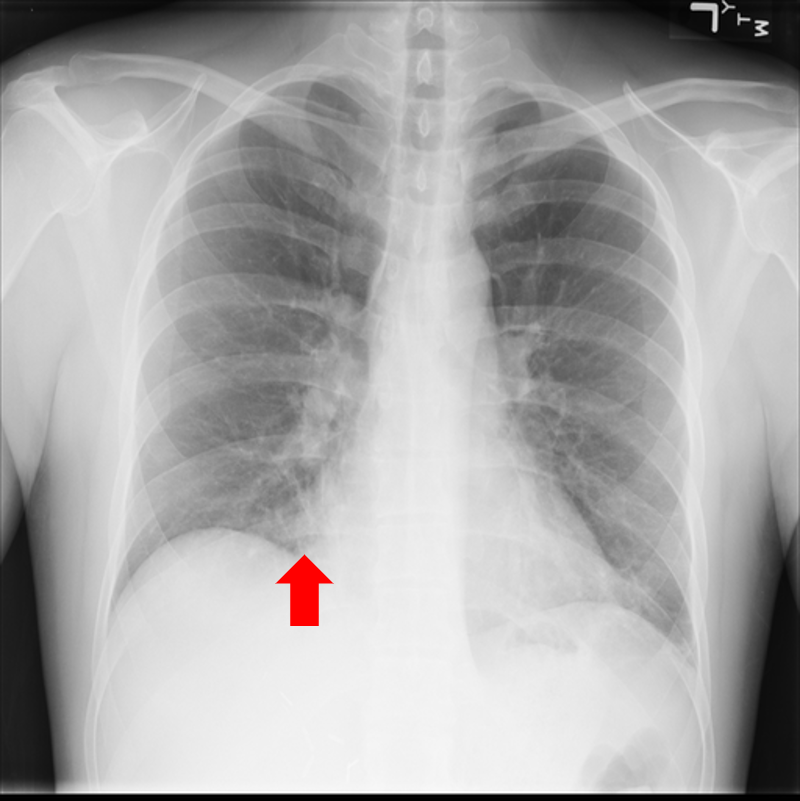

(h) Pneumoperitoneum

Figure 10: Typical CXRs with a lesion from among the top 1,000 CXRs most likely to have an abnormality according to the logarithm posterior probability out of the 13,863 abnormal CXRs excluding those with a pneumonia-like lung opacity. The lesion is indicated with a red arrow if applicable.

Figure 10 shows CXRs suggested to have an abnormality different from pneumonia-like lung opacity with the logarithm posterior probability. These CXRs are the top 1,000 CXRs most likely to have an abnormality out of the 13,863 abnormal CXRs.